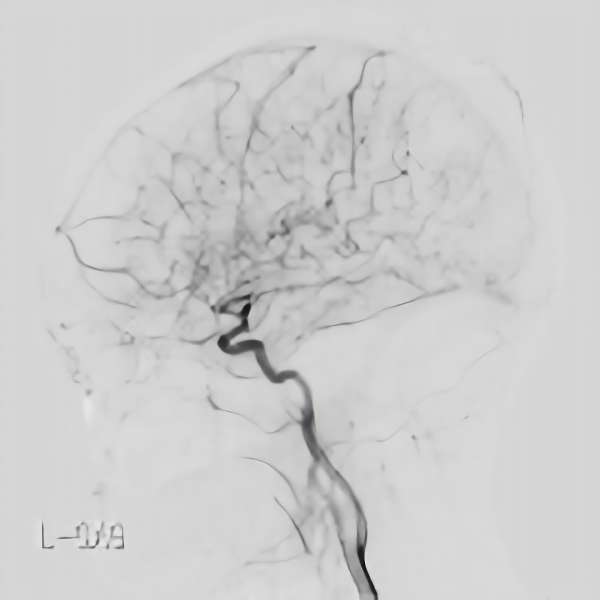

脳血管撮影

手術前

手術後